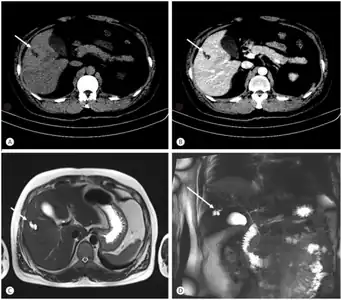

![]() | |

| Turbo spin echo T2-weighted axial MRI of Caroli disease, showing cystic dilatations of bile ducts (shown as white).[1] | |